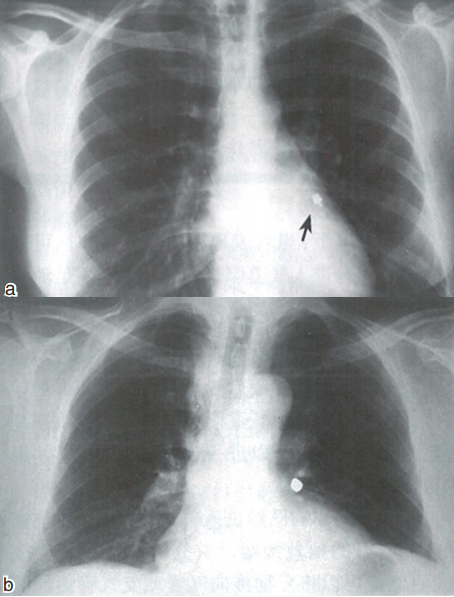

X线确认异物位置   如果不能看到异物(可能已经误咽),应当进行X线检查,确定异物的位置。在没有完成X线检查之前,不能让患者离开诊室。如果临床症状和体征不能明确异物是进入消化道或气道,医师应当护送(如果可行)患者到附近医院的急诊科或影像科,影像科医师常建议给患者拍胸部前后位及侧位片(图11)或腹部平片。如果X线检查能见到异物,当然希望是在腹部X线片上(例如食管或胃里),而不是在胸片上(例如支气管内)。无论何种情况,只要异物被认定在消化道或气道,必须寻求相关专业医师帮助(例如消化科、胸外科或麻醉科医师)。一般是由相关专业医师直接进行后续处理。但如果影像科医师不能明确异物位置或存在其他有关异物定位及并发症方面的问题,应当立即请相关专业医师会诊。通常情况下,患者表现出的症状和体征可以帮助确定异物是进入气道(气管、支气管)还是消化道,异物误吸后的突发症状和体征,包括突然发作的咳嗽、呛咳、哮鸣音和气短。90%以上的患者在异物误吸后1小时内有以上症状和体征。但也有少数患者在异物误吸后6小时才出现明显的症状和体征。根据病情的严重程度,1/3的患者可立刻出现窒息现象,体征可以进一步发展到发绀,并出现严重缺氧的相关症状。

图11 影像学检查(a为胸部前后位片,黑色箭头所指为橡皮抛光杯;b为金属冠误患者左肺部)